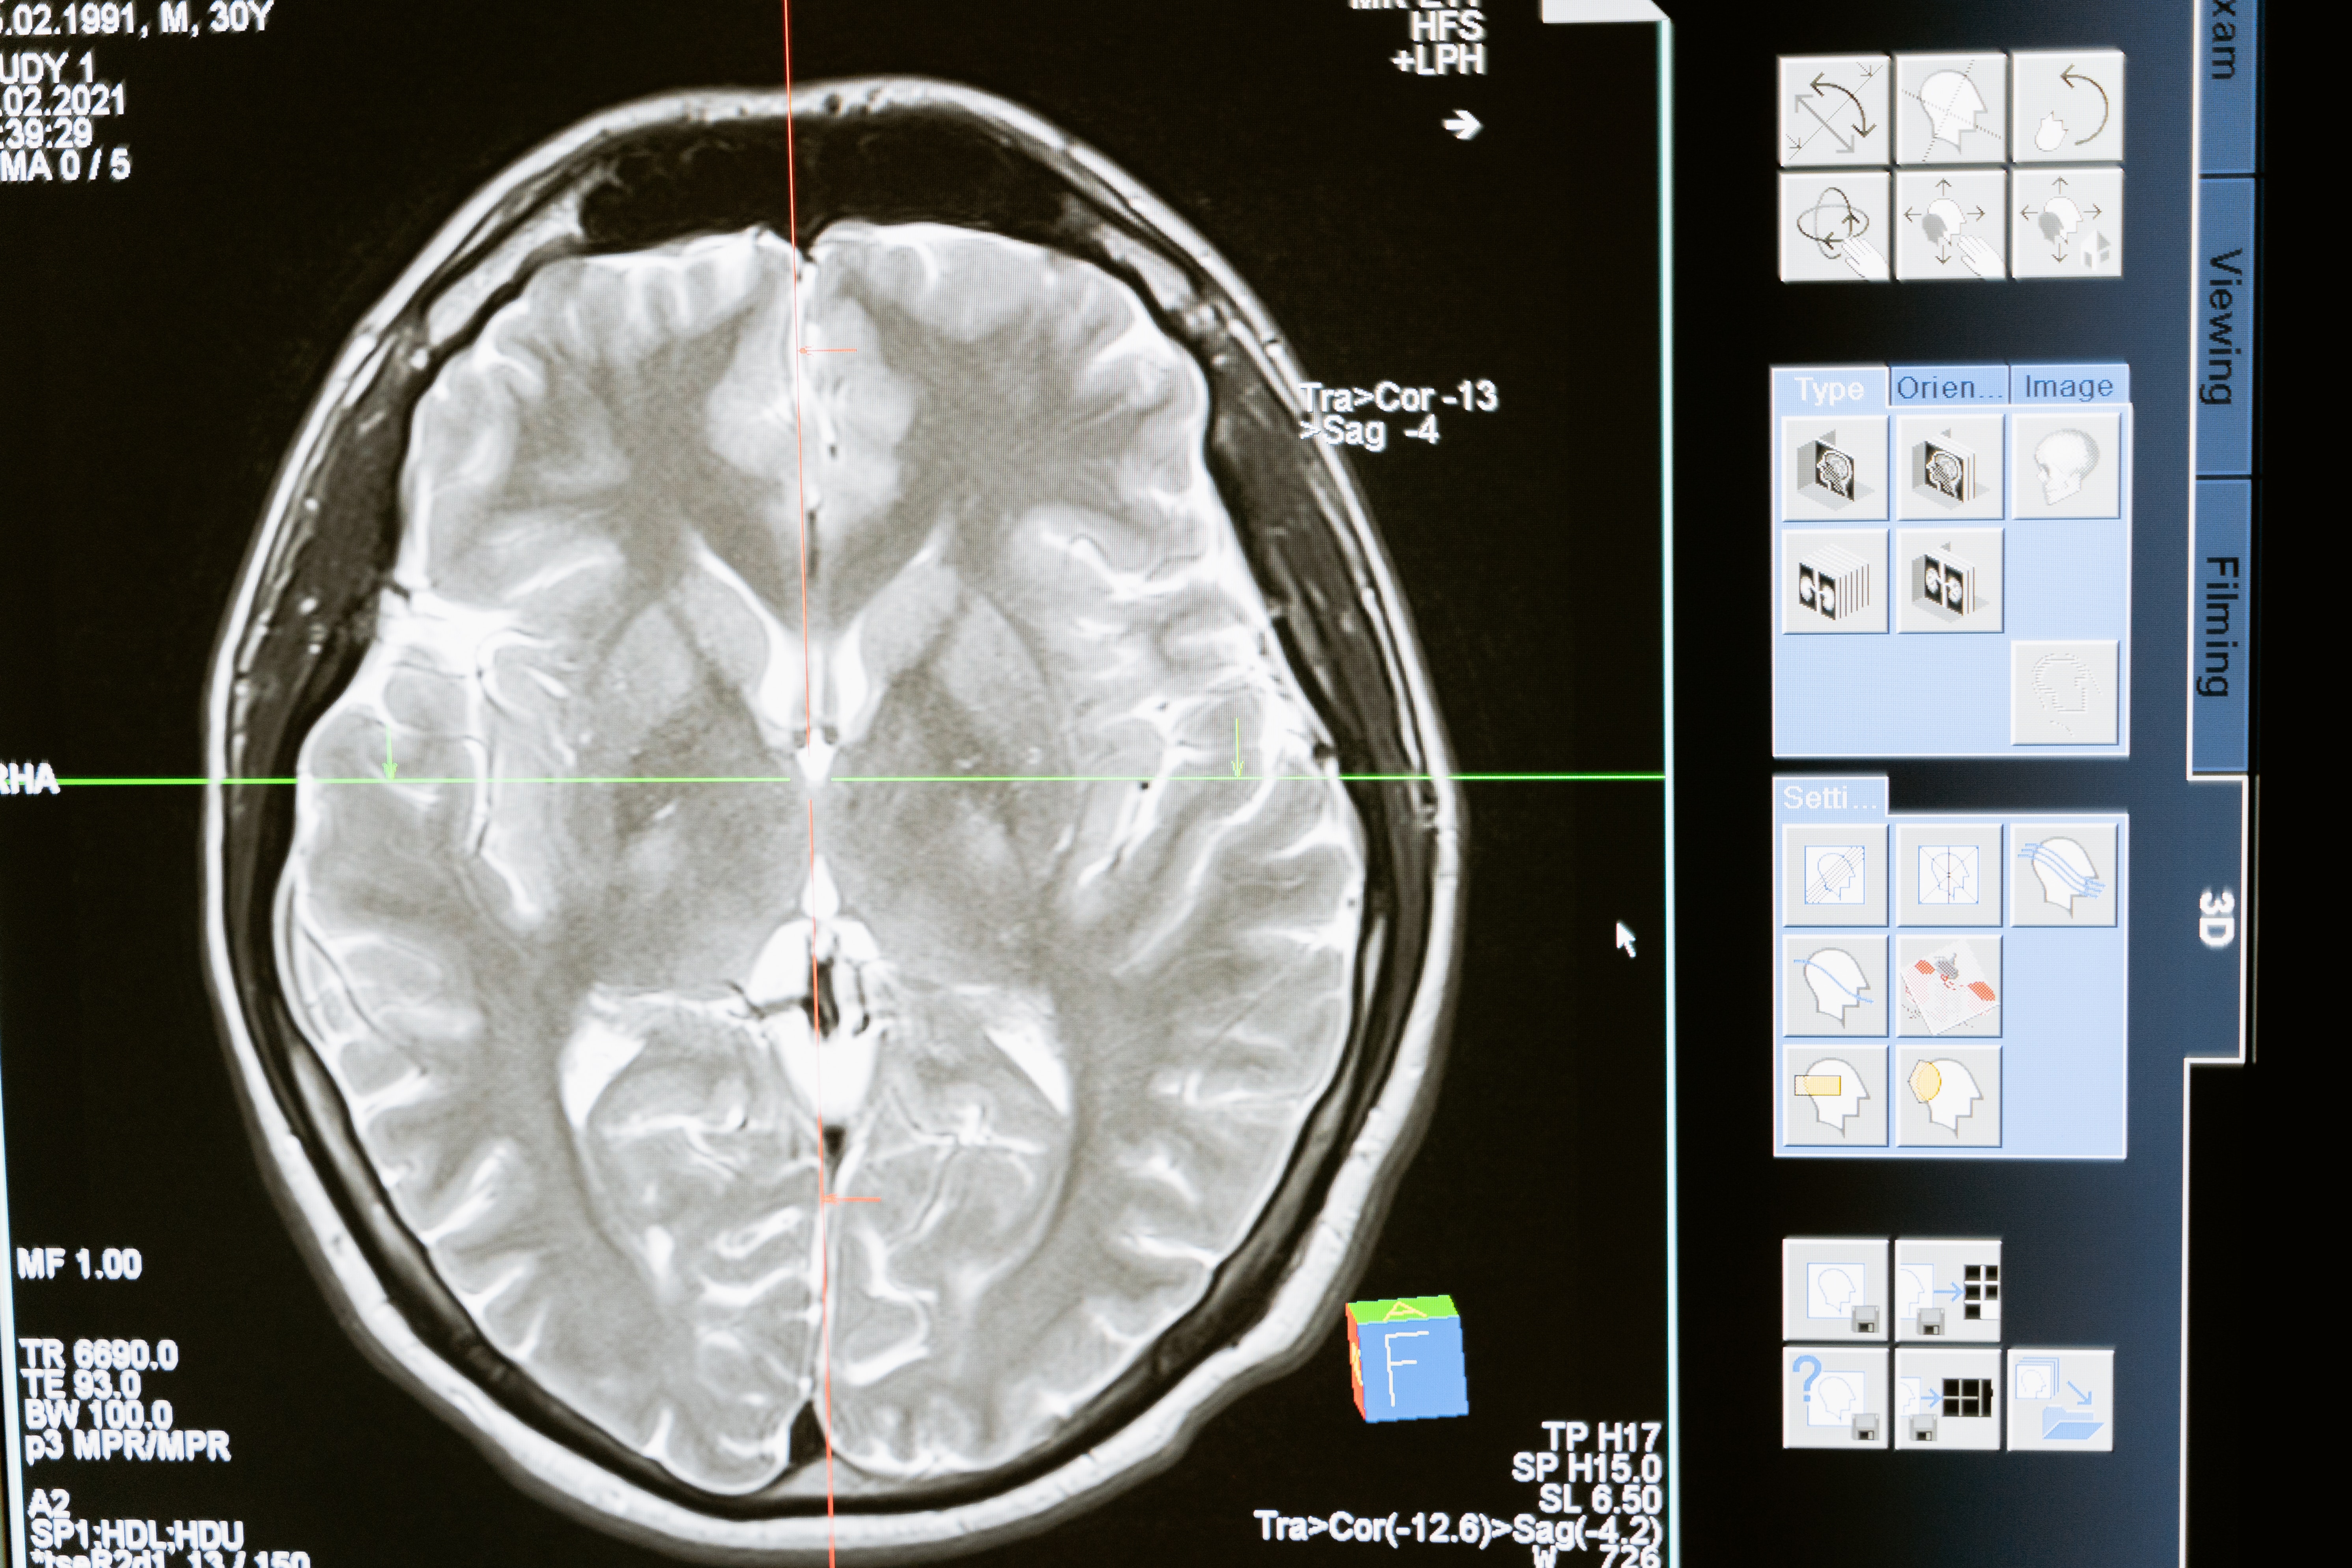

Stroke is a serious brain condition in which the blood vessels present in brain ruptures or bleeds or when there is a blockage in the blood supply of the brain. This rupture or blockage causes sudden death of brain cells or neurones. A stroke can cause permanent brain damage, long-term disability or even death. It is categorised in mental illness. Every year, more than 795,000 people in the United States have a stroke. About 610,000 of these are first or new strokes. About 185,000 strokes—nearly 1 in 4—are in people who have had a previous stroke. About 87% of all strokes are ischemic strokes, in which blood flow to the brain is blocked and not only United States is affected by stroke problem, there is a drastic change in the cases of stroke every year all over the world.